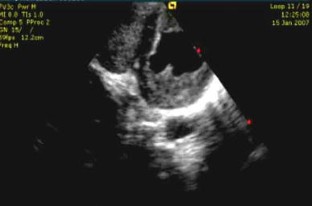

Fig. 2

Movie clip 3 Two-dimensional echocardiogram in a parasternal long axis view showing obliteration of the right ventricle apex as well as involvement of the left ventricle lateral wall with thickening of the posterior mitral leaflet. (MOV 2332 kb)

Movie clip 4 Two-dimensional echocardiogram in a parasternal short axis view showing complete replacement of the right ventricular cavity. Infiltration is seen in the left ventricle also. (MOV 2089 kb)